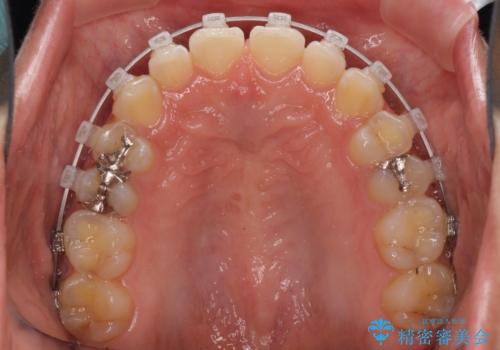

前歯の隙間を閉じたい 短期間でのワイヤー矯正

- 上の前歯の隙間を気にして来院された患者様です。

インビザラインの自己管理は自信がないとのことで、ワイヤー矯正により隙間を閉じていくこととしました。

下の前歯が上の前歯を突き上げるように咬合するため、咬み合わせの位置を改善しながら隙間を閉じていきました。

元々の歯並びが悪くなかったため、9ヶ月で綺麗に仕上がりました。

すきっ歯は後戻りを起こしやすいため、上下ともに歯の裏側を細いワイヤーで固定した上で、リテーナーのマウスピースを装着していただいています。